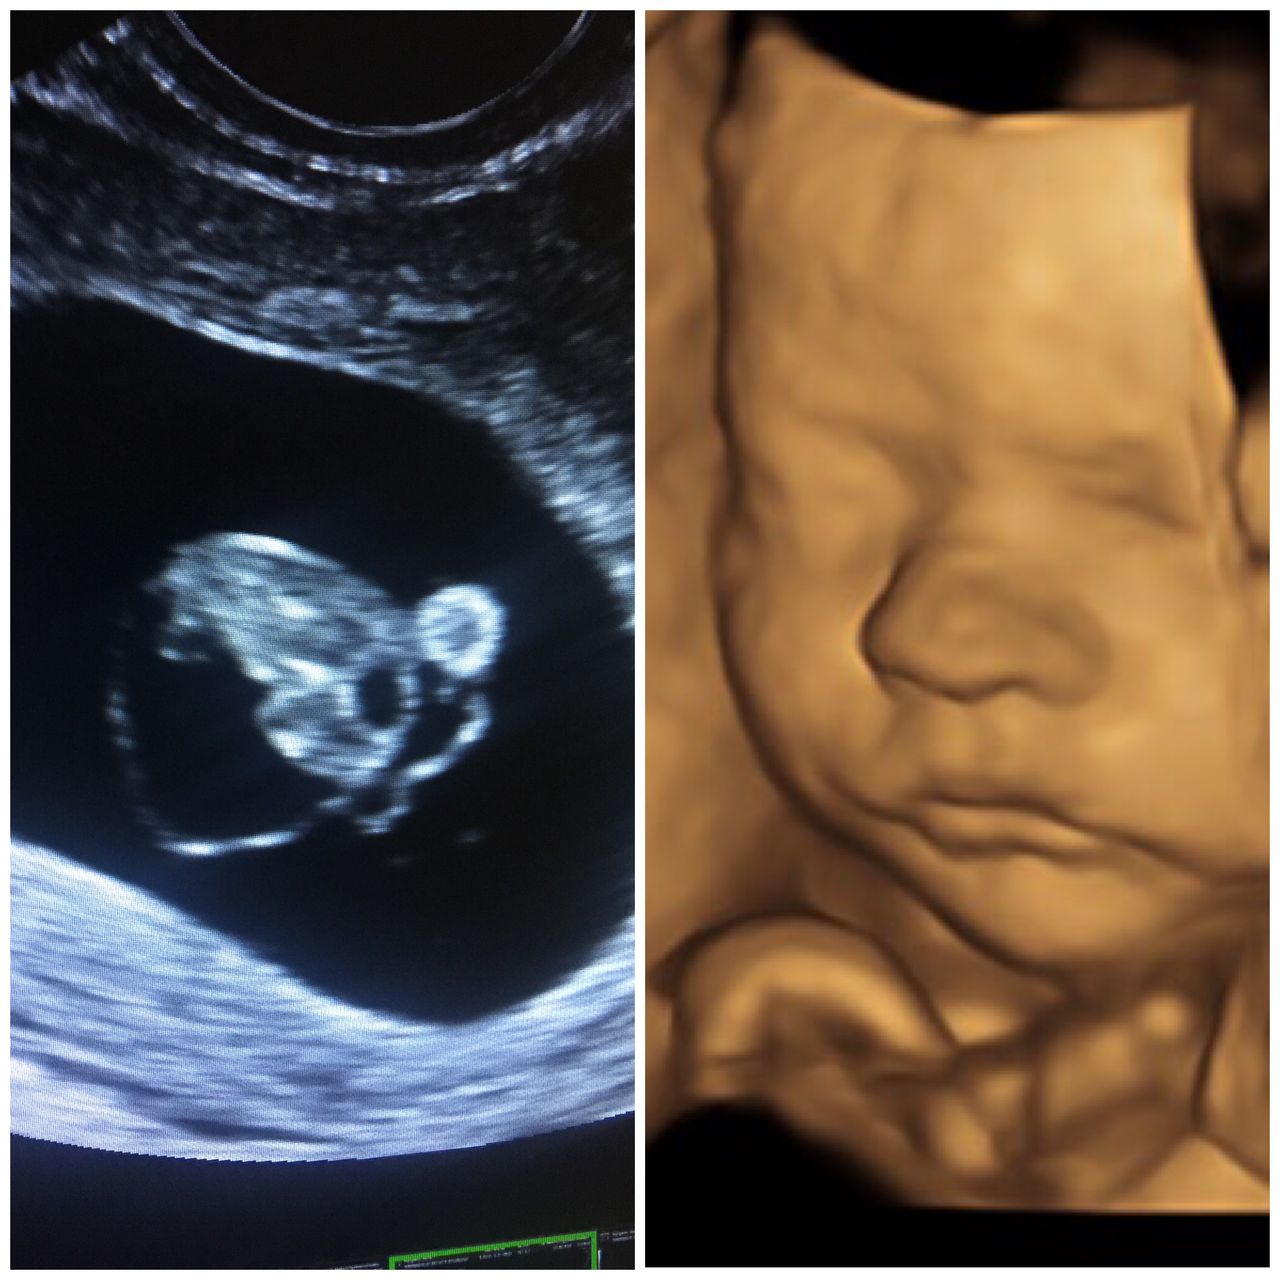

Certyfikowany ultrasonografista Fetal Medicine Foundation(FMF NT Specjalist) z uprawnieniami do wykonywania badań prenatalnych .

1.USG prenatalne wykonujemy pomiędzy 11 a 13 w 6 dni ciąży . Najlepsze rezultaty otrzymujemy gdy badanie przeprowadzamy pomiędzy 12 a 13 tygodniem ciąży . Pacjentka która chce aby badanie było bardziej szczególowe i w większym stopniu wykrywało wady genetyczne (82%vs 92 % wykrytych zespół wad genetycznych )powinna zgłosić się na wizytę z wynikiem tekstu PAPPA (test z krwi )

2. badanie II trymestru wykonujemy pomiędzy 18-22 tygodniu . Jeśli lekarz prowadzący nie zaleci inaczej (lub były stwierdzane inne nieprawidłowości we wcześniejszych badaniach - badanie najlepiej wykonać w 22 tygodniu

3. Badanie III trymestru najlepiej wykonać w 28 tygodniu ciąży

Jestem bardzo zadowolona z przebiegu wizyty. Pan doktor bardzo dokladnie i szczegolowo opisuje obraz usg. Wszystko zostało nam objaśnione. Badanie wykonywane na wysokiej jakości sprzęcie. Dodatkowo obejrzelismy maluszka w obrazie 4D. To bylo badanie prenatalne III trymestru, żałuję ze poprzednie dwa badania prenatalne zostały wykonane w innym gabinecie.